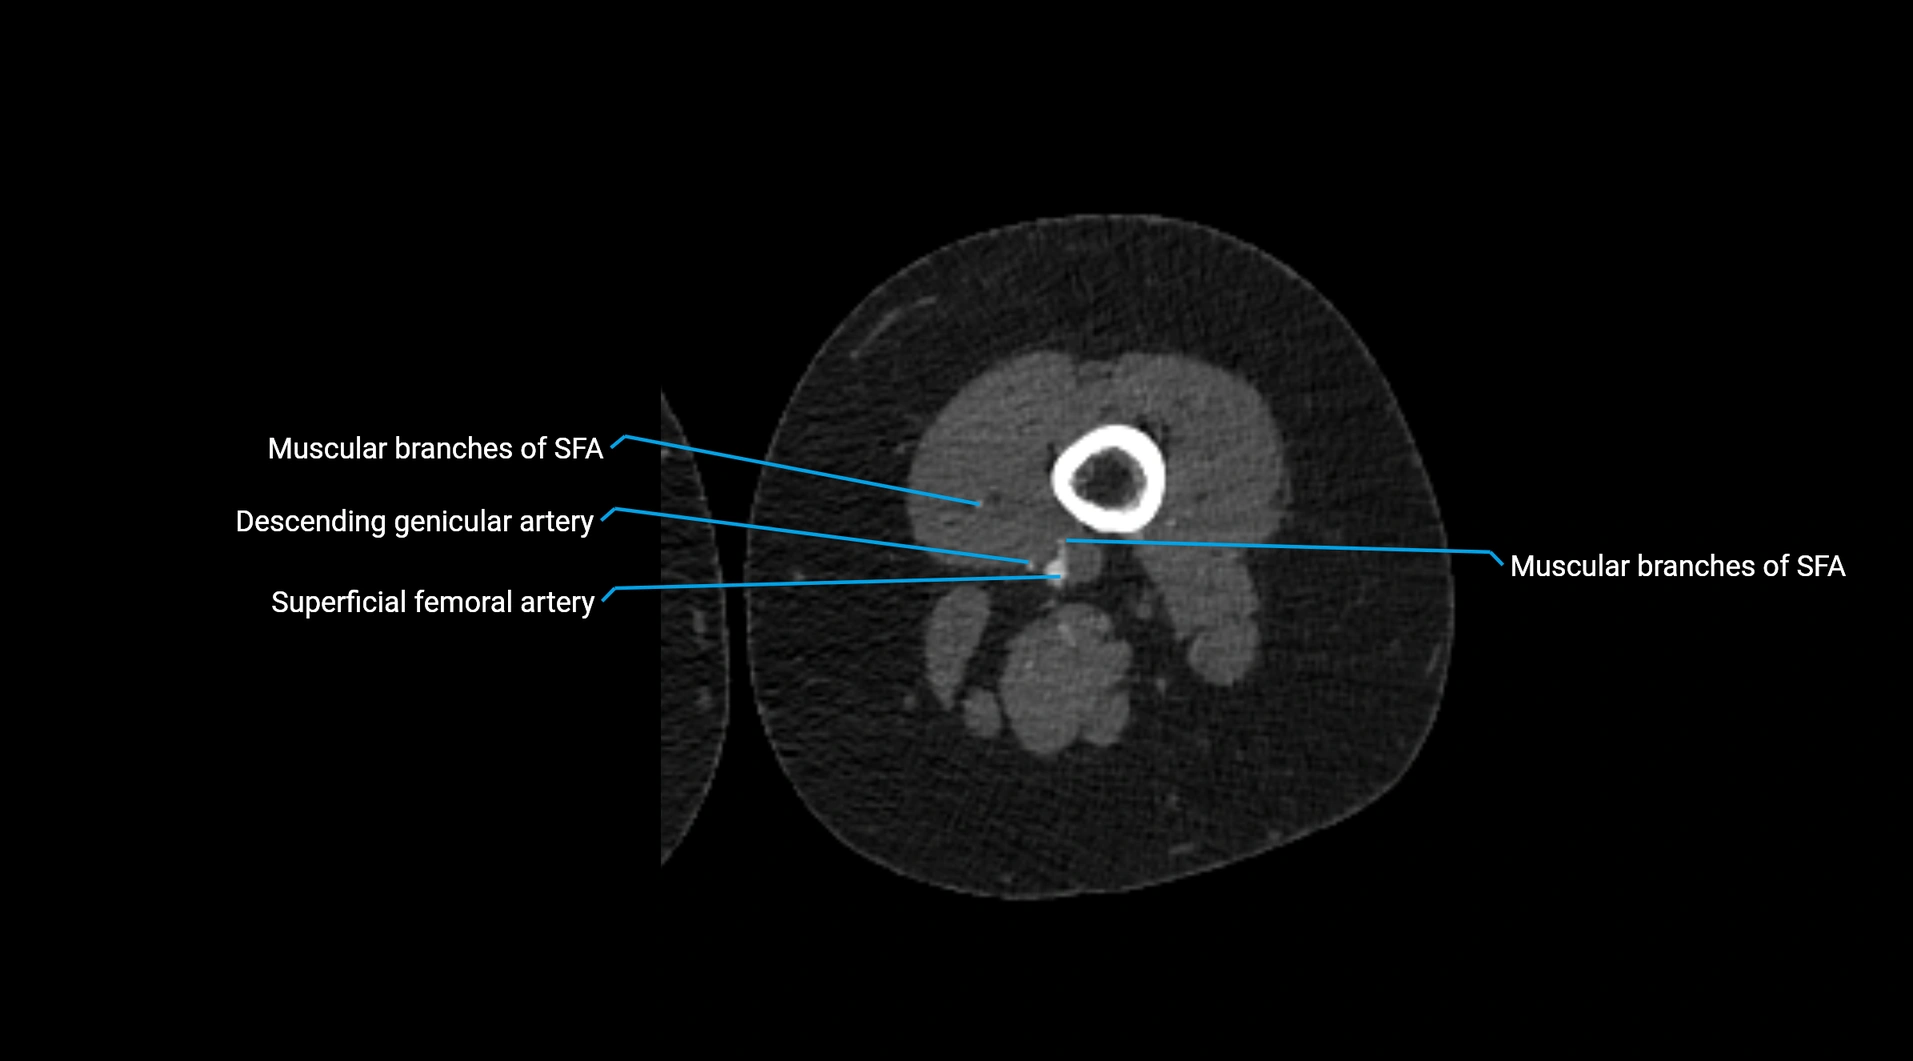

Contrast-enhanced CT (CTA):

• Gold standard for abdominal aortic imaging

• Provides excellent detail of lumen, wall, aneurysm, thrombus, and branch vessels

• Multiplanar and 3D reconstructions help in aneurysm measurement, stent graft planning, and dissection evaluation

• Detects acute rupture, traumatic injury, or occlusion with high sensitivity